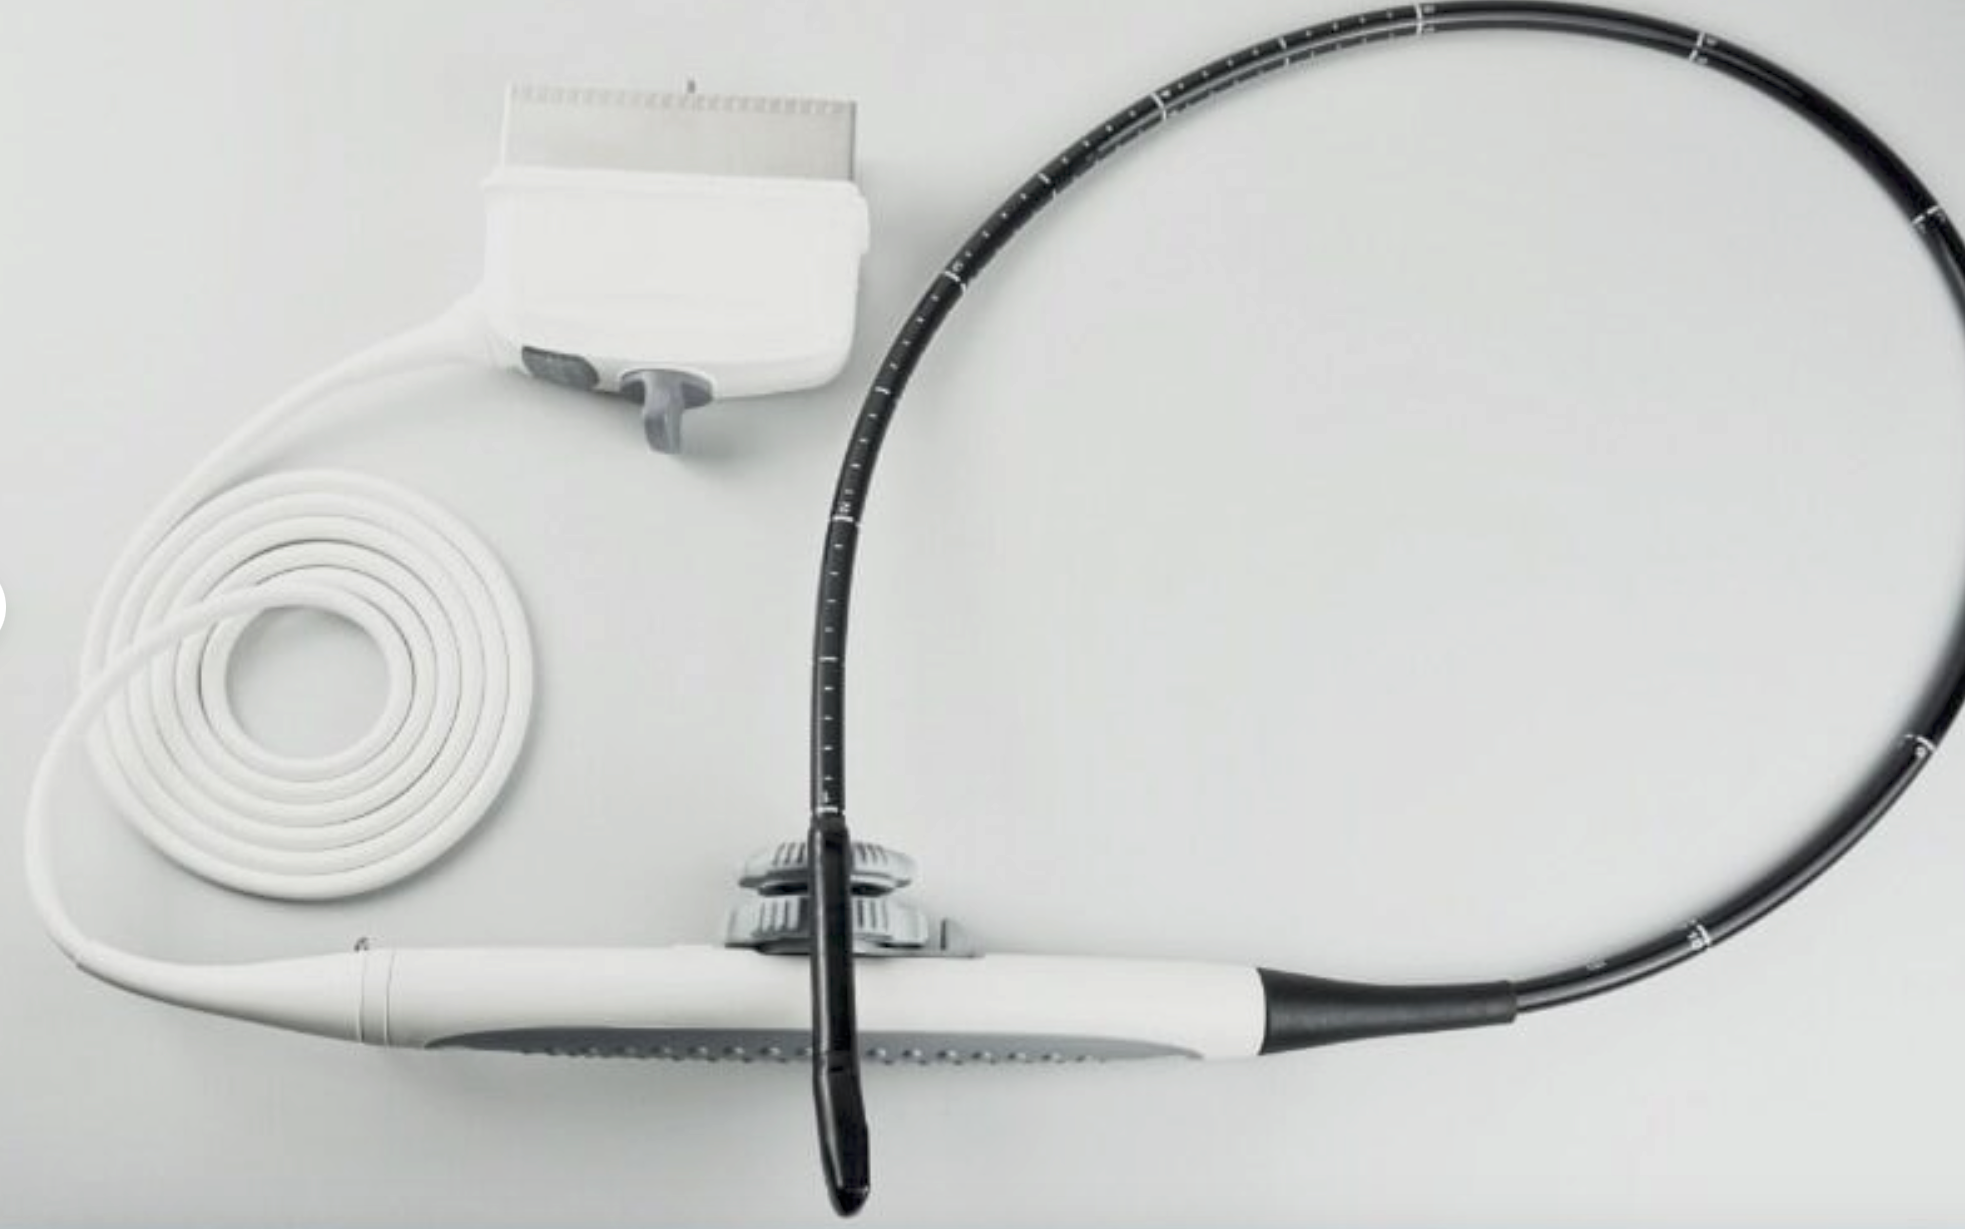

The Philips CX50 Portable Ultrasound System emerges as an exceptional choice for medical professionals seeking top-tier cardiac and vascular imaging capabilities. This seller refurbished unit has undergone rigorous inspection, cleaning, and restoration processes to ensure its return to peak working condition, almost indistinguishable from its original state, even if the original packaging may not be present.

With a special focus on cardiac echo and vascular diagnostics, this system includes a warranty that underscores our commitment to quality and customer satisfaction. The Philips CX50 is renowned for its stellar performance and reliability in various clinical settings.